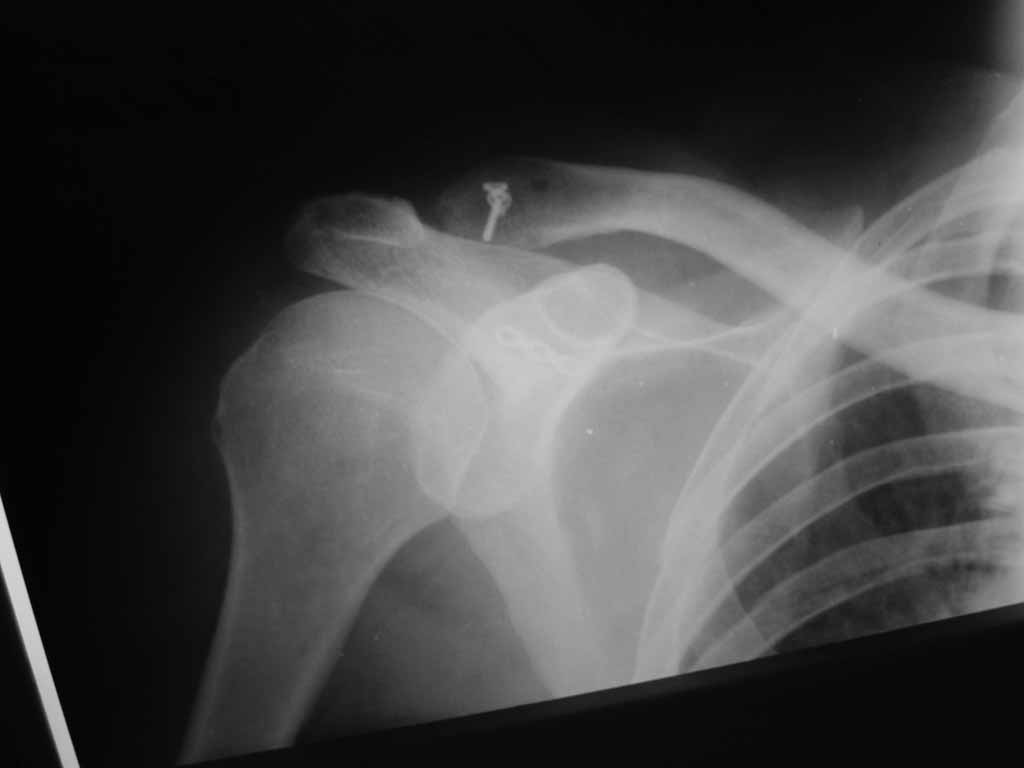

Re: Лечение вывиха акромиального конца ключицы

В Пензенской ОКБ им. Н.Н.Бурденко мы в свежих случаях (до 3 недель) проводим либо фиксацию по Веберу (2 спицы и стягивающая проволочная петля), либо фиксацию крючковидной пластиной (если больной согласен ее приобрести).

В застарелых случаях необходимо кроме фиксации сустава дополнительно проводить пластику ключично-клювовидной связки любым доступным способом.

В свежих случаях (до 3 недель) глубоко индифферентно, чем фиксировать, главное - низвести в сустав. Делаем по Ли (субакромиально изогнутым стержнем, потом в косынку, стержень удаляется под местняком через 6 недель), либо крючковидной пластиной.

Если начать сначала, то предпочтение отдаем класификации Роквуда. Использовал разные методики оперативного лечения. Откыртое вправление и фиксация спицами акромиально-ключичного сустава с пластикой ключично-клювовидной связки лавсаном, а также баз пластики звязки. Результаты одинаковые. Мое мнение, что в свежем случае можна обойтись и без вмешательства по пластике ключично-клювовидной связки если мы открыто вправляем вывих и фиксируем его например спицами - главное сблизить вправленнием волокна связки. Использовал методику по Веберу и крючковидную пластинку. По Веберу нравится, особенно если нужна хорошая фиксация. Проблем с миграцией, переломом и прочими проблемами при ипользовании спиц не было ни разу. Пластинка - красиво, быстро, для активных пациентов или спортсменов подходящий метод лечения, хотя и дороже. Застарелый случай был только один. Тогда оперировали с открытым вправлением, фиксацией спицами и пластикой ключично-клювовидной связки - результат хорошый.